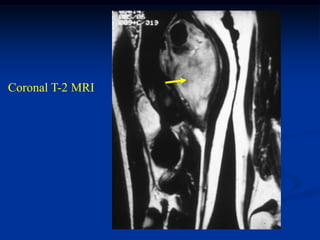

Case #253

29 year male

recent fracture ulna

18 months later

with desmoid tumor

at fracture site

Sagittal T-2 MRI 18 months later with desmoid tumor

Axial T-2 MRI at 18 months